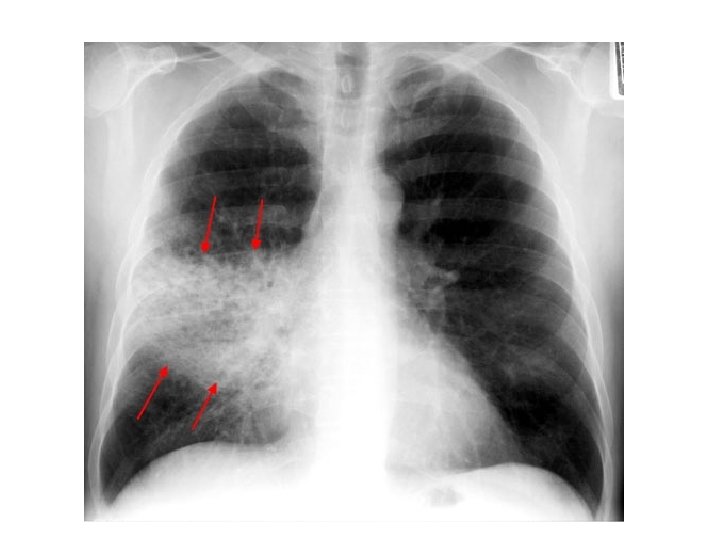

Cannonball Metastases of the Lungs • • • Causes; Renal cell carcinoma Endometrial carcinoma Choriocarcinoma Prostate cancer